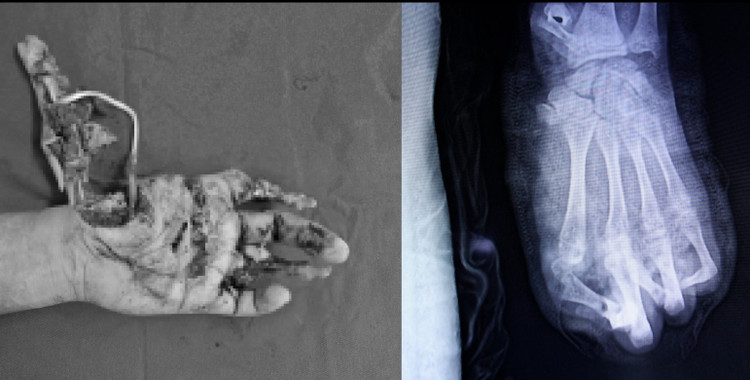

Hình ảnh tổn thương thực tế và trên phim chụp - Ảnh BVCC

Người bệnh nhập viện ở giờ thứ ba sau tai nạn, với bàn tay trái dập nát gần như hoàn toàn, kèm theo vết thương phần mềm vùng đùi trái.

“Bàn tay của người bệnh bị dập nát gần như hoàn toàn. Những tổn thương do pháo nổ hay hỏa khí thường rất phức tạp, khả năng phục hồi các đơn vị ngón tay là vô cùng khó khăn”, bác sĩ cho biết.

Dù được cấp cứu và phẫu thuật khẩn trương, sau nhiều nỗ lực của ê-kíp, các bác sĩ chỉ có thể giữ lại được 2 trong số 5 ngón tay cho người bệnh.

Toàn bộ vùng gan tay và cổ tay bị dập nát nặng, khiến quá trình điều trị dự kiến kéo dài, với nhiều cuộc phẫu thuật tiếp theo. Tiên lượng lâu dài, người bệnh có thể chỉ phục hồi được một phần chức năng rất hạn chế của bàn tay.